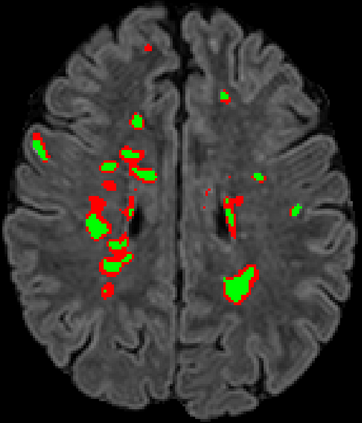

Recently, segmentation methods based on Convolutional Neural Networks (CNNs) showed promising performance in automatic Multiple Sclerosis (MS) lesions segmentation. These techniques have even outperformed human experts in controlled evaluation conditions such as Longitudinal MS Lesion Segmentation Challenge (ISBI Challenge). However state-of-the-art approaches trained to perform well on highly-controlled datasets fail to generalize on clinical data from unseen datasets. Instead of proposing another improvement of the segmentation accuracy, we propose a novel method robust to domain shift and performing well on unseen datasets, called DeepLesionBrain (DLB). This generalization property results from three main contributions. First, DLB is based on a large group of compact 3D CNNs. This spatially distributed strategy ensures a robust prediction despite the risk of generalization failure of some individual networks. Second, DLB includes a new image quality data augmentation to reduce dependency to training data specificity (e.g., acquisition protocol). Finally, to learn a more generalizable representation of MS lesions, we propose a hierarchical specialization learning (HSL). HSL is performed by pre-training a generic network over the whole brain, before using its weights as initialization to locally specialized networks. By this end, DLB learns both generic features extracted at global image level and specific features extracted at local image level. DLB generalization was validated in cross-dataset experiments on MSSEG'16, ISBI challenge, and in-house datasets. During experiments, DLB showed higher segmentation accuracy, better segmentation consistency and greater generalization performance compared to state-of-the-art methods. Therefore, DLB offers a robust framework well-suited for clinical practice.